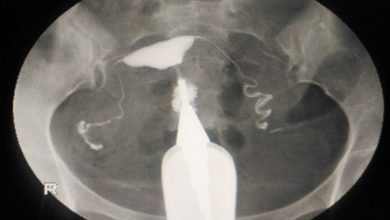

HSG, rahim ve tüplerin radyo-opak madde (boyalı madde) kullanılarak görüntülendiği bir radyolojik yöntemdir. Kadın-Doğum hekiminin radyoloji ünitelerinde uygulamasını yaptığı bu…

Bu muayene çoğu zaman, rahmin (uterus) ve fallop tüplerinin daha yakından incelenmesi amacıyla yapılır. Histerosalpingografi, rahmin (histero) ve fallop tüplerinin…